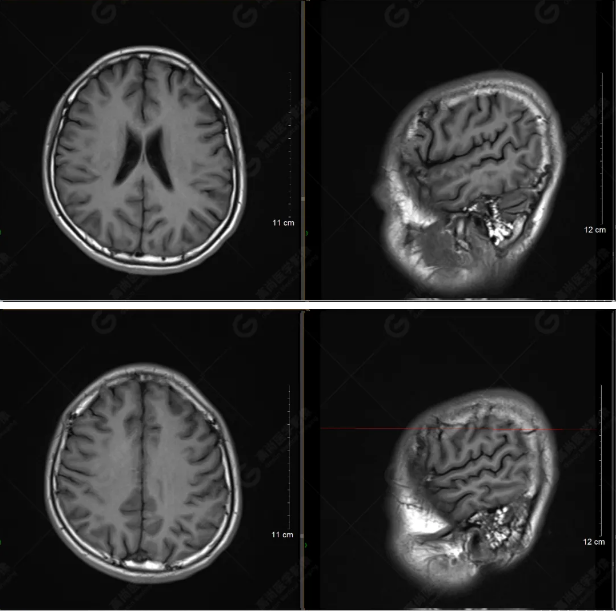

以下是T1WI軸位掃描及矢狀位掃描:

雙側(cè)大腦半球?qū)ΨQ,灰白質(zhì)對比正常,顱內(nèi)未見異常信號影。腦室系統(tǒng)未見擴(kuò)大,中線結(jié)構(gòu)居中。腦溝、裂未見增寬。幕下小腦、腦干未見異常。矢狀位示垂體形態(tài)、大小級信號未見異常。所示左側(cè)乳突內(nèi)見多發(fā)短T1長T2信號影。

顱腦MRI平掃未見明顯異常,左側(cè)乳突內(nèi)積血,建議補(bǔ)充SWI檢查。(左側(cè)為薄層原始圖像,右側(cè)為后處理5mm圖像)